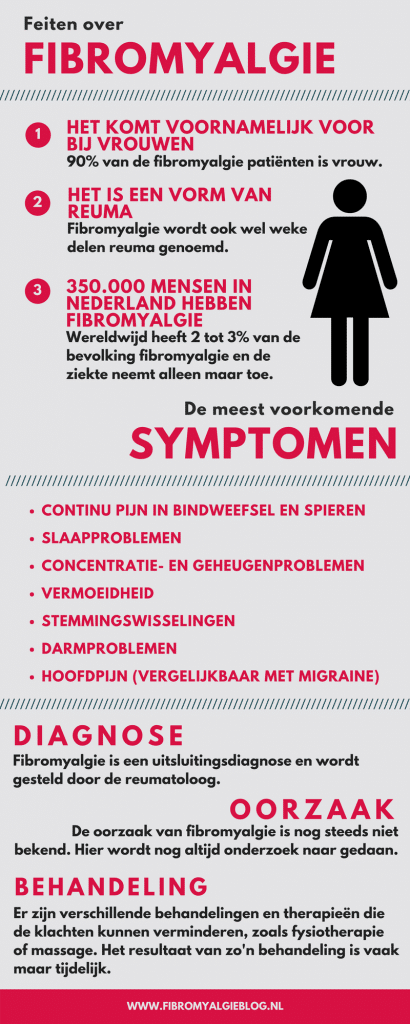

Niet alleen ontdekte de neuroloog een whiplash in mijn nek, ook was deze man de eerste die de woorden weke delen reuma liet vallen, in de volksmond ook wel fibromyalgie genoemd. Zijn advies: leren omgaan met de pijn. Dat kon het beste door middel van revalidatietherapie.

Ik sloot een abonnement af bij de plaatselijke sportschool. Door het sporten kreeg ik de fibromyalgie redelijk onder controle. De pijn in mijn onderrug en nek negeerde ik vaak of als de pijn echt te vurig werd, bestreed ik deze met zware pijnstillers. Regelmatig bezocht ik de huisarts nog voor deze klachten. Het standaard antwoord bleef steeds dat het echt allemaal door de fibromyalgie kwam. Het begon steeds meer in mijn hoofd te wringen, dat er meer aan de hand was, dan het lichamelijk onderzoek deed uitwijzen.

Na de uitslag van de second opinie moest ik helaas terug naar de orthopeed die de eerste onderzoeken had gedaan, want zo gaat dat in de medische wereld. Al snel werd er een behandelplan ingezet om de pijn zoveel mogelijk te verzachten. Ik werd doorverwezen naar de pijnpoli. Waar ik al snel de term polyartrose voor het eerst hoorde vallen. Vanaf dat moment kreeg ik te maken met de eerste pijnblokkades in mijn nek en schouder. En kreeg ik voor de heftige momenten een Tens-apparaatje zodat ik door middel van kleine stroomstootjes de zenuw zelf kon prikkelen, waardoor de pijn werd geblokkeerd.